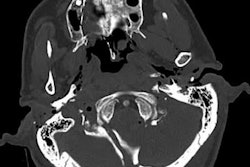

Postmortem CT (a) and postmortem CT angiography (b-d) scans of a 59-year-old woman who died of internal exsanguination soon after Whipple surgery. All images courtesy of RSNA.The group acquired CT and CT angiography scans of the bodies within five days of death. A forensic pathologist and a radiologist, both with more than five years of experience in reading postmortem CT angiography data, evaluated the scans individually. A second forensic pathologist conducted the autopsy for each case on the same or following day.